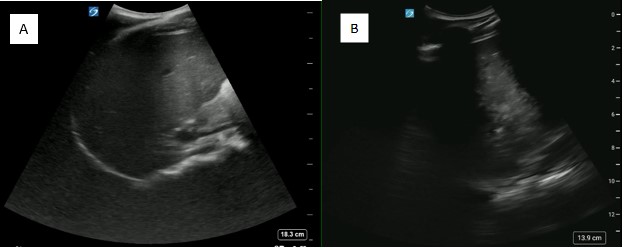

A 16-year-old male with history of recurrent shoulder dislocation and arthroscopic labral repair, presented with acute right shoulder pain after colliding with another player during basketball. The physical exam was notable for obvious right shoulder deformity, with an intact neurovascular exam. POCUS revealed an anterior shoulder dislocation without humeral fracture. After discussion with the family, the decision was made to proceed with an interscalene nerve block. The block was performed, and the shoulder was subsequently reduced successfully, confirmed by post-reduction POCUS (Figure 1). The patient was noted to have an asymptomatic ipsilateral diaphragm paralysis following the nerve block, which resolved within an hour, and he was discharged without complication. He did not require any opioids or procedural sedation throughout his ED stay, and tolerated both procedures well.

May2025-Pedi Interscalene_Fig 1.jpgFigure 1. A) Pre-reduction anterior shoulder dislocation B) Post-reduction